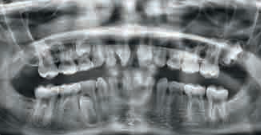

- l’agénésieOn parle d’agénésie dentaire lorsqu’il manque une plusieurs dents. Certaines dents sont plus souvent absentes c’est le cas des incisives latérales supérieures, puis les dents de sagesse. : absence congénitale d’une ou plusieurs dentsLes dents sont des organes de la bouche, constitués des tissus les plus minéralisés du corps humain. Chez l’homme deux générations de dents se succèdent : les dents de laits et les dents définitives. Elles permettent la mastication : première étape de la digestion. Elles sont au nombre de 20 pour les dents de lait et 32 pour les dents définitives. (cf aussi dents de lait).L’agénésieOn parle d’agénésie dentaire lorsqu’il manque une plusieurs dents. Certaines dents sont plus souvent absentes c’est le cas des incisives latérales supérieures, puis les dents de sagesse. touche le plus souvent les dentsLes dents sont des organes de la bouche, constitués des tissus les plus minéralisés du corps humain. Chez l’homme deux générations de dents se succèdent : les dents de laits et les dents définitives. Elles permettent la mastication : première étape de la digestion. Elles sont au nombre de 20 pour les dents de lait et 32 pour les dents définitives. (cf aussi dents de lait) de sagesse, les incisives latérales supérieures ou les prémolaires.

- l’hyperdontieL’hyperdontie, dents supplémentaires, concerne souvent la région antérieure du maxillaire, avec des dents surnuméraires pouvant gêner l’éruption normale. : dentsLes dents sont des organes de la bouche, constitués des tissus les plus minéralisés du corps humain. Chez l’homme deux générations de dents se succèdent : les dents de laits et les dents définitives. Elles permettent la mastication : première étape de la digestion. Elles sont au nombre de 20 pour les dents de lait et 32 pour les dents définitives. (cf aussi dents de lait) supplémentaires. L’hyperdontieL’hyperdontie, dents supplémentaires, concerne souvent la région antérieure du maxillaire, avec des dents surnuméraires pouvant gêner l’éruption normale., plus rare, concerne souvent la région antérieure du maxillaire, avec des dentsLes dents sont des organes de la bouche, constitués des tissus les plus minéralisés du corps humain. Chez l’homme deux générations de dents se succèdent : les dents de laits et les dents définitives. Elles permettent la mastication : première étape de la digestion. Elles sont au nombre de 20 pour les dents de lait et 32 pour les dents définitives. (cf aussi dents de lait) surnuméraires pouvant gêner l’éruption normale.

AgénésieOn parle d’agénésie dentaire lorsqu’il manque une plusieurs dents. Certaines dents sont plus souvent absentes c’est le cas des incisives latérales supérieures, puis les dents de sagesse.

HyperdontieL’hyperdontie, dents supplémentaires, concerne souvent la région antérieure du maxillaire, avec des dents surnuméraires pouvant gêner l’éruption normale.

Un diagnostic précoce, souvent réalisé à l’aide de radiographies, permet une prise en charge adaptée : OrthodontieL'orthodontie une spécialité qui consiste à prévenir ou à traiter les anomies de position des dents. On parle plus largement d’orthopédie dento-faciale, lorsque l’on s’attache aux positions des dents et des mâchoires. Après examens, le dentiste pourra engager un traitement avec un appareillages fixé aux dents ou amovible pour permette un placement des dents harmonieux et fonctionnel., prothèses ou chirurgie peuvent être envisagées pour restaurer fonction et esthétique.